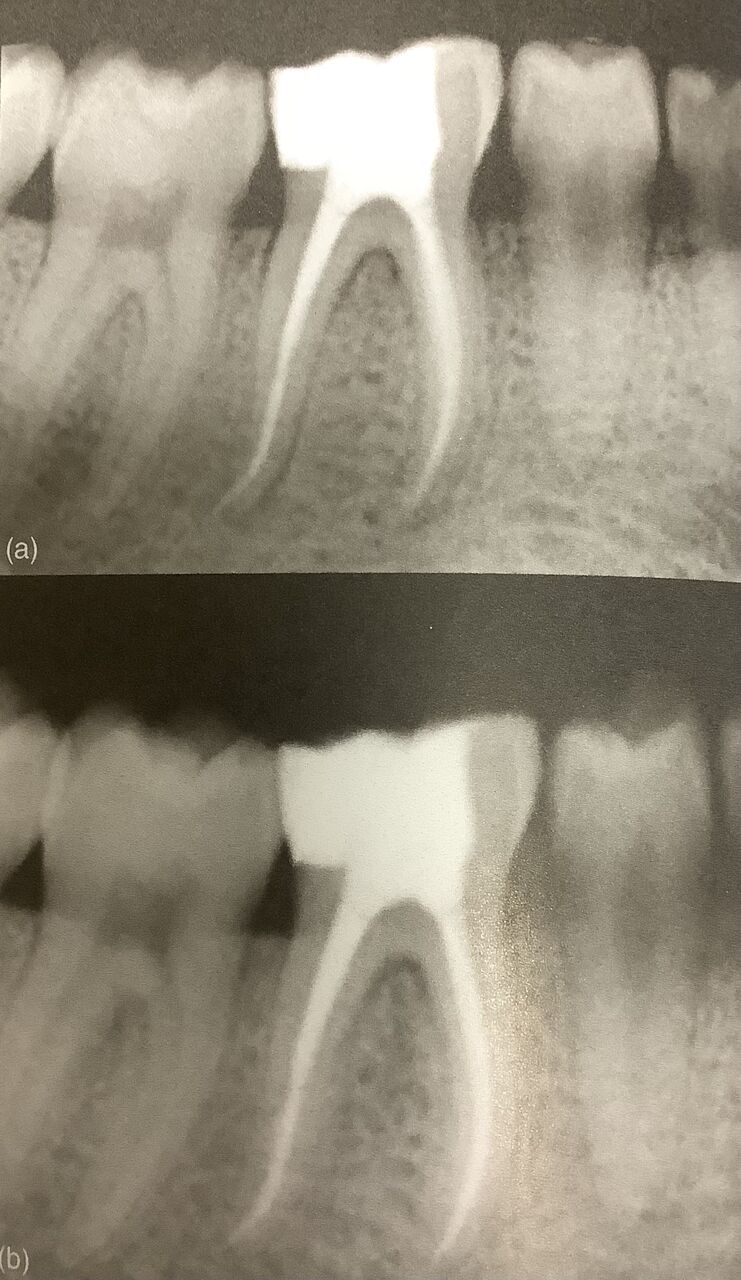

全部の神経が見つかり、複雑な根管を理想的な長さで適切に削って、消毒し、詰められたので

この根管治療の予後は素晴らしいでしょう。